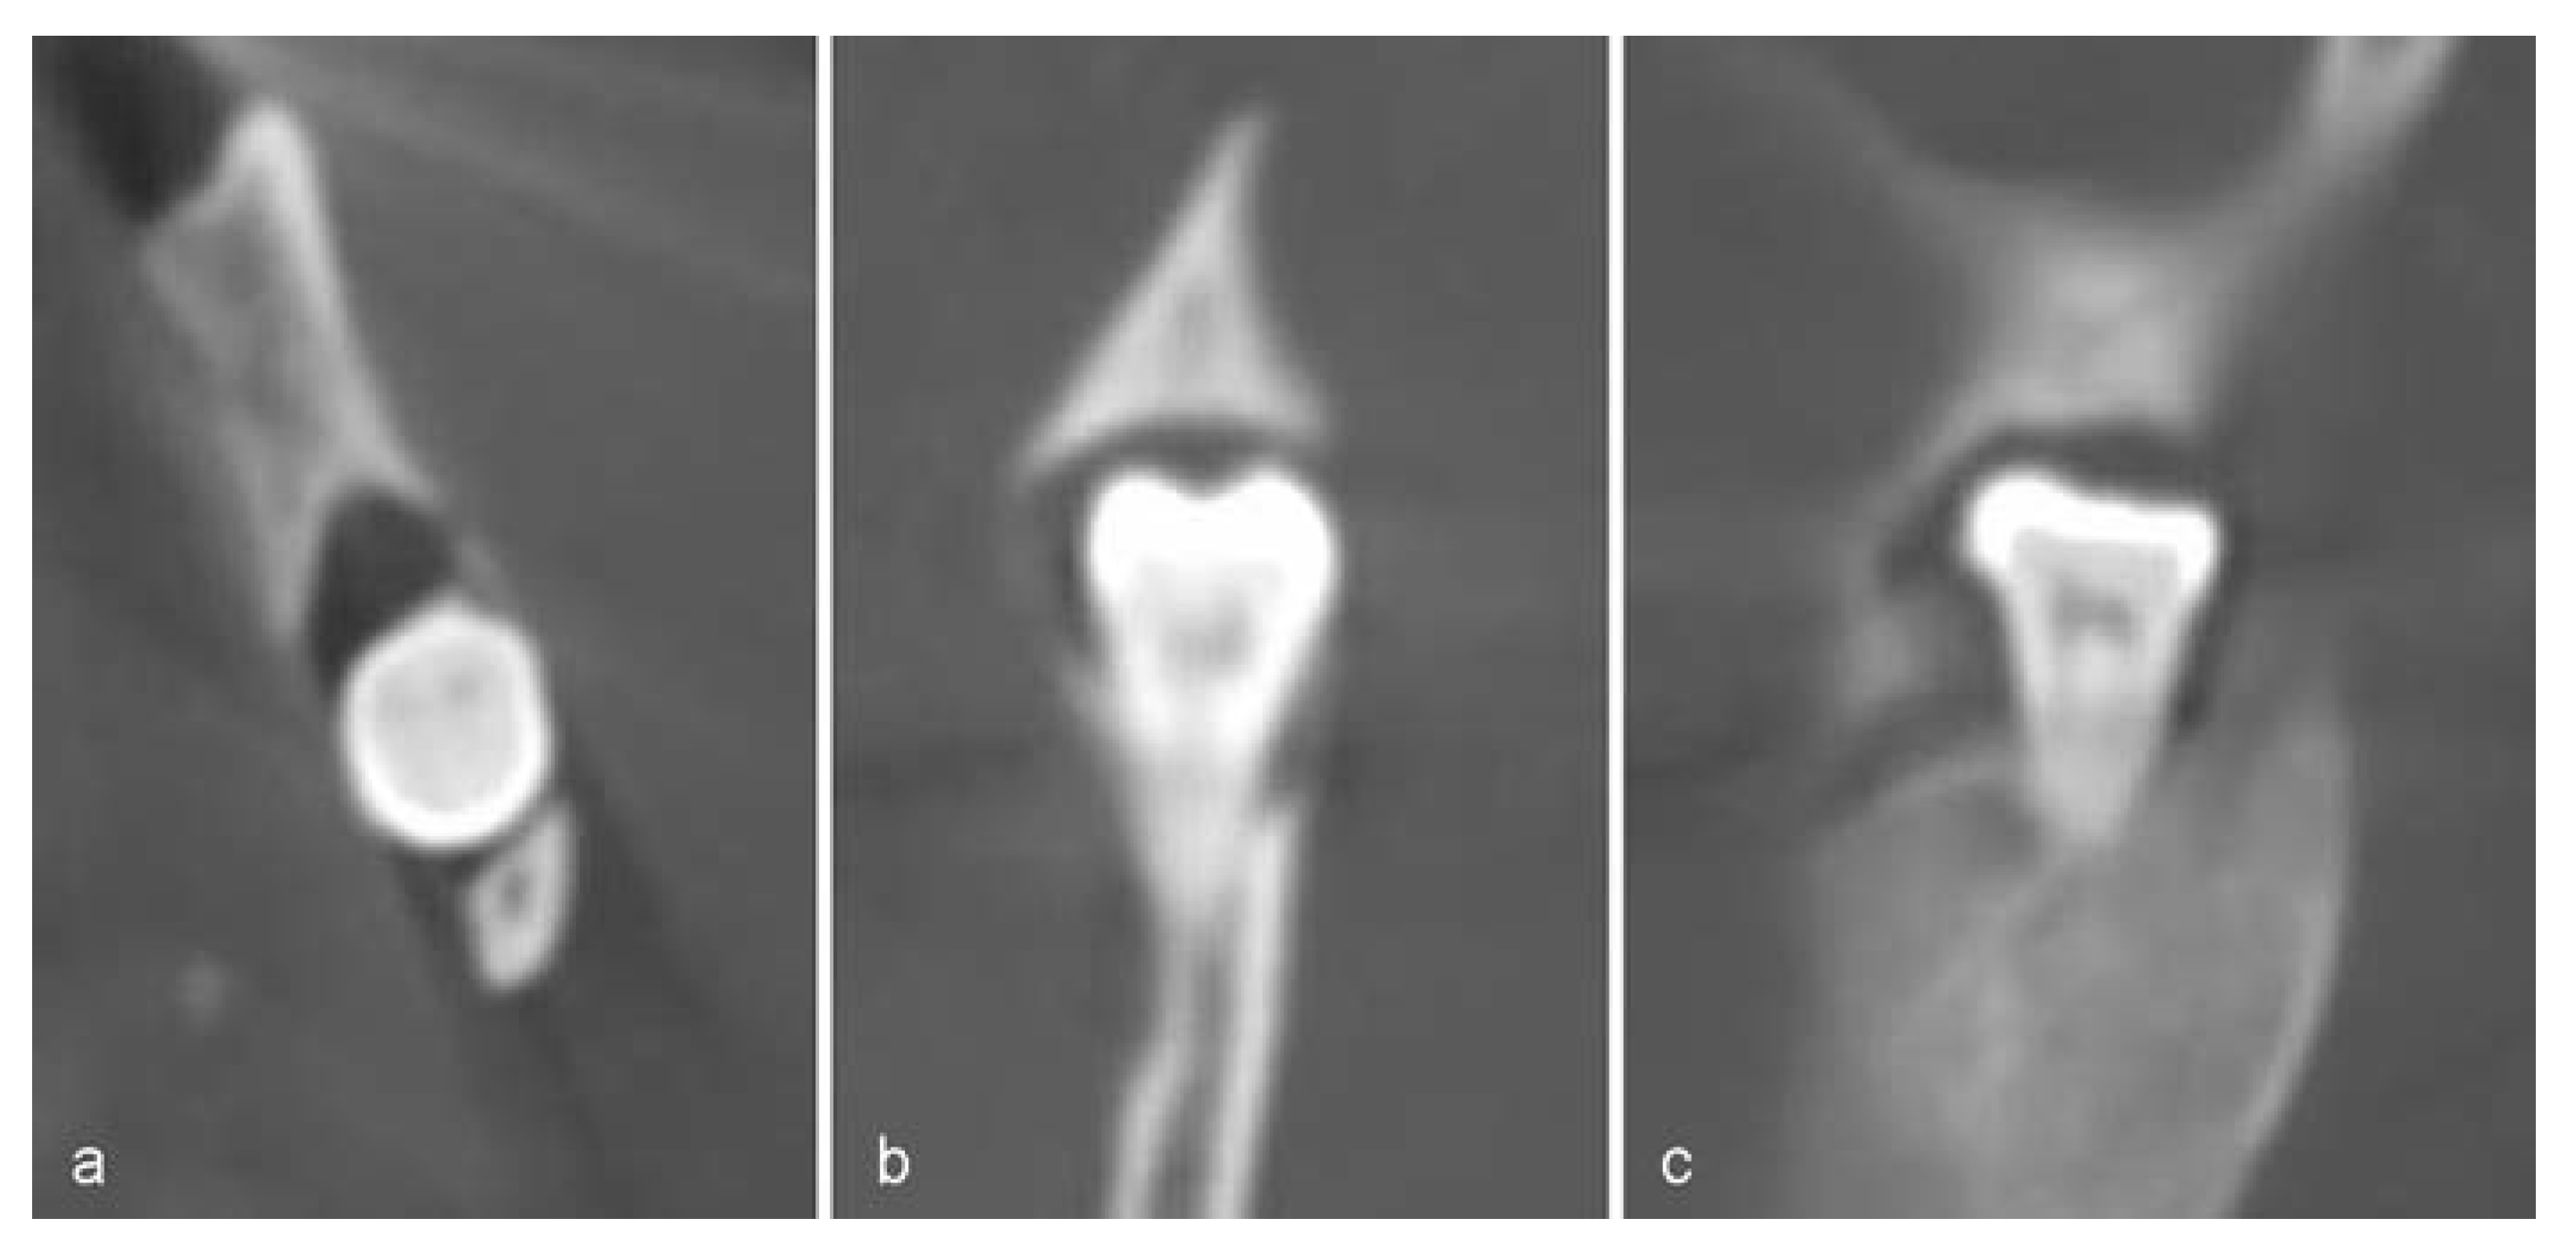

Report of a Case

![]() |